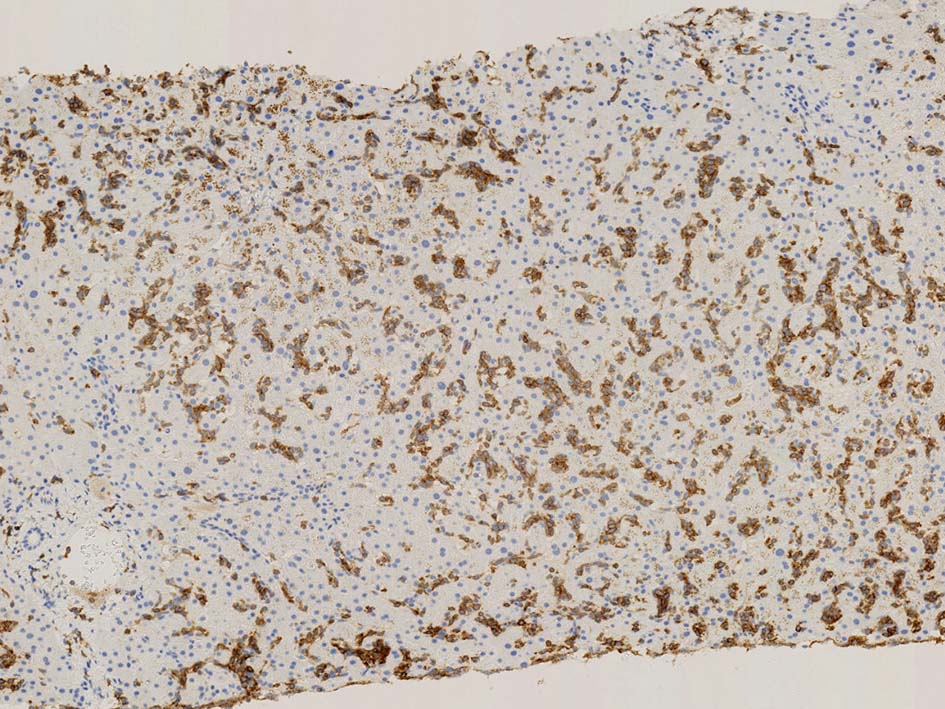

類洞内で増殖する腫瘍細胞はCD3+, CD7+のT-cellであるがCD5発現が弱く, 異常なT-cellである.

CD4は類洞内皮/macrophageの一部が陽性であるが, 類洞内腫瘍細胞の多くは陰性を示す(陽性と間違えないこと). CD8陰性. CD20陽性リンパ球はごく少ない.

TIA1は陽性であるが, granzymeBは陰性細胞が多い.